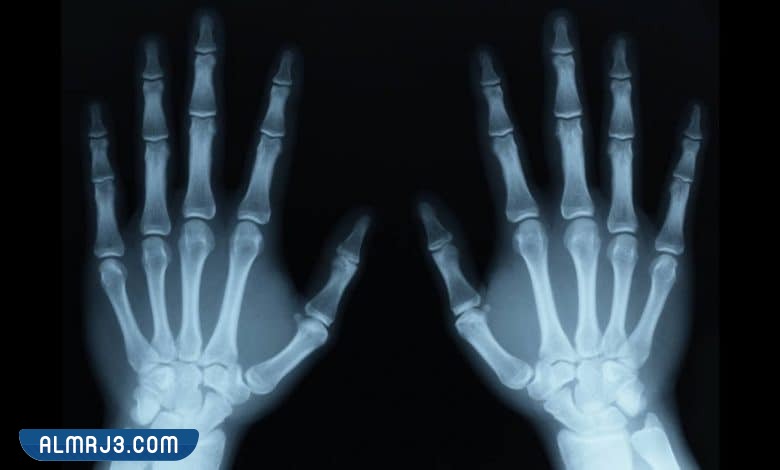

نعم، تحجب المجوهرات والمعادن الأشعة السينية، وتمنعها من الوصول للعضو المصاب في الجسم والتقاط صور واضحة له لأنها تؤدي إلى تشتيت الأشعة لذا يجب خلع المجوهرات والمعادن وقطع الملابس التي تحتوي على أجزاء معدنية قبل البدء في إجراء التصوير الداخلي للجسم بالأشعة السينية.

- اكتشاف وجود كسور في العظام أو شظايا داخل الجسد.

- التخفف من الملابس وخلع كافة المعادن والمجوهرات والنظارة سواء أكانت نظارة طبية أو شمسية.